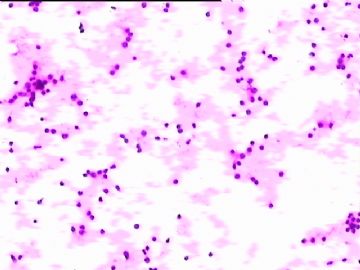

78y,男,胸水。 大家看看那些小于淋巴细胞的东东。

孢子?

图6感觉象是污染的孢子之类的东西。好好回忆一下,制片过程?容器?有没有污染的 可能?

但,最后一图的组织细胞内吞噬现象,怎么解释。

离体的细胞在一定的时间内还是活细胞,所以我推测吞噬细胞可能还是有一定的吞噬功能的。不过,确实也不能就排除了在活体内的微生物感染的可能。结合临床应该能够得到一定程度的澄清。